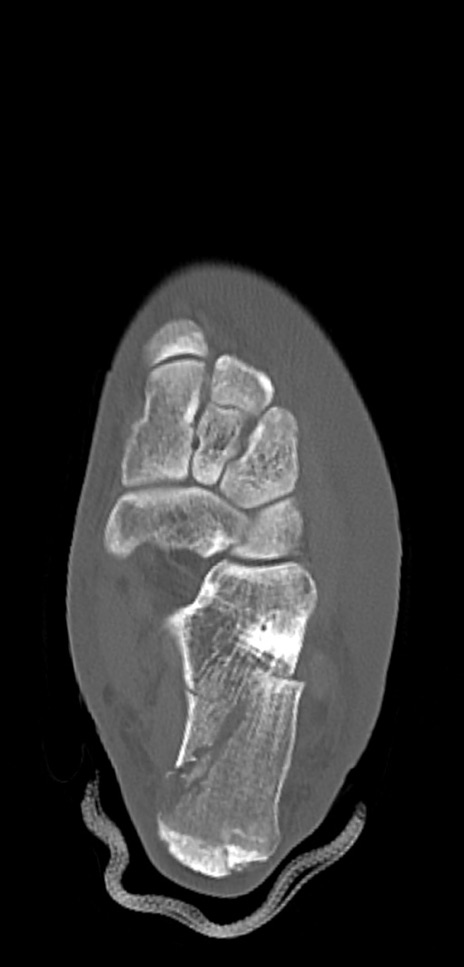

症例37 左足関節CT(横断像)

左足関節CT

矢状断像